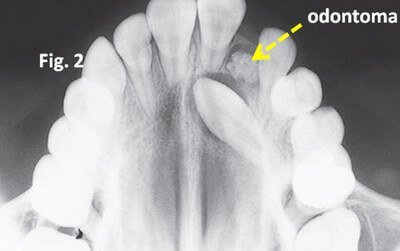

Odontome or composite odontoma is the category which is not widely accepted by dentists as a classification of supernumerary teeth because the term depicts a tumor. The mass consists of different types of tissues. There are two subcategories. The first one is complex composite odontoma wherein the dental tissue is not organized. The second one is compound composite odontoma which externally resembles a normal tooth.

Picture 10: Odontome or Composite Odontoma

Image Source: orthocj.com